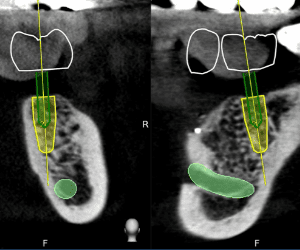

全球動態醫療導航最高精準度0.2mm,最先進的時時導航技術,可以手術當下即時反映出植牙鑽針的角度、深度、位置等資訊,精準定位植體位置。

降低風險及副作用

導航技術讓醫師能夠及時掌握植體在牙脊中的深度與角度,避免傷害到鼻竇腔與神經管,同時手術開刀範圍縮小,達到真正的微創植牙,相對也大幅降低術後的疼痛與腫脹感。

最新牙科導航儀,只需讓病患拍攝一次的斷層掃描,避免過量的輻射劑量,同時輔助牙醫師在植體定位更精準,取代傳統醫師僅憑手感植牙,降低手術風險,提高診療效率。